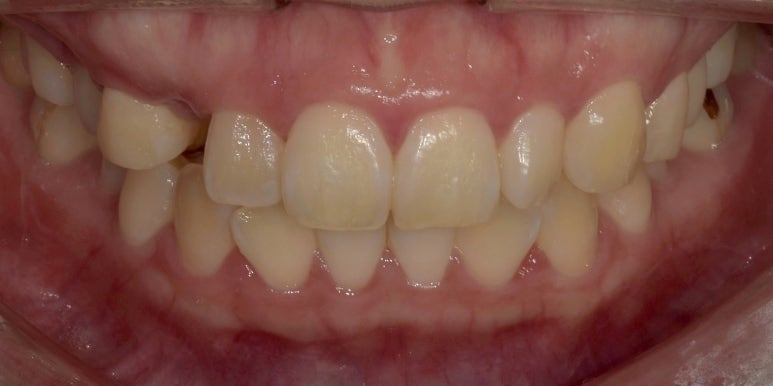

치료 후 사진

2023-04-14

치료전후사진

(전) 2023-03-02 (후) 2023-04-14

어떤가요? 결손되었던 치아는 브릿지로 완벽하게 메워졌고, 왜소치도 다른 치아와 유사하게

그리고 10번대 치아와 대칭이 잘 맞는 모습이 보이실 겁니다.

치아 색상도 전체적으로 밝아졌고, 잇몸라인도 둥글고 고르게 변한 것을 확인하실 수 있습니다.